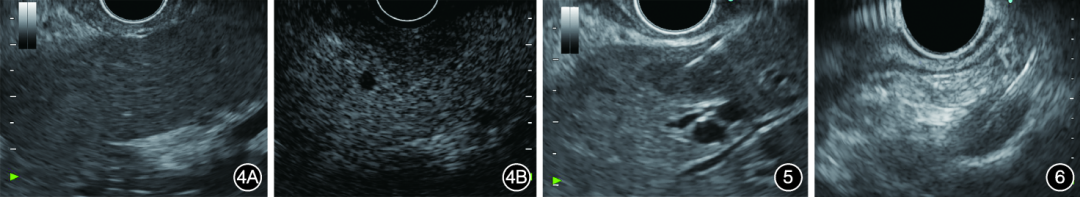

本中心共进行了9例肝脏转移灶CH⁃EUS⁃FNA(图1~图6)。选用25G(5例)、22G(5例)穿刺针,扇形穿刺,以生理盐水预充穿刺针道,连接10mL负压注射器或慢撤导丝,在没有ROSE的情况下,推荐穿刺肝脏病灶2×20次。

图1胰腺癌病灶行超声内镜造影1A:胰腺癌病灶在超声内镜下表现为低密度;1B:胰腺癌病灶在谐波造影增强超声内镜下表现为异质性、低增强图2胰腺癌病灶弹性成像显示病灶较硬图3胰腺癌病灶穿刺图4胰腺癌肝转移病灶行超声内镜造影4A:超声内镜下未见肝脏转移灶;4B:谐波造影增强超声内镜下见肝脏转移灶图5肝脏转移灶穿刺图6门静脉穿刺